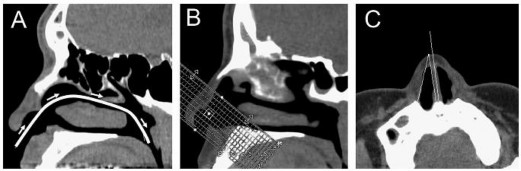

Myung-Whan Suh và cộng sự đo góc van mũi trong qua CT scan trên 38 mũi của người Hàn Quốc khỏe mạnh (Hình 1.12).

Hình 1.12 Hình tái tạo trên CT scan để đo góc van mũi trong. (A) trục đường thông khí; (B) các lát cắt vuông góc trục thông khí; (C) lát cắt có diện tích nhỏ nhất là vùng van mũi, góc van mũi trong được đo giữa thành mũi bên và vách ngăn.

“Nguồn: Myung-Whan Suh, 2005” [79]

Kết quả góc van mũi trong trên CT scan là 21,60 4,50. Kết quả này so sánh với góc van mũi trong ở người châu Âu da trắng trong nghiên cứu của Poetcker và cộng sự [92] đo được là 11,40 2,60 với cùng phương pháp đo. Khác biệt này có ý nghĩa (p<0,001) như vậy góc van mũi trong ở người châu Á lớn hơn góc van mũi trong ở người châu Âu da trắng.

Góc van mũi trong đo qua nội soi là 19,30 3,60. Nghiên cứu cho thấy tính thống nhất của phép đo trên CT scan rất cao (hệ số tương quan là 0,828, p<0,001) trong khi phép đo qua nội soi thì thấp (hệ số tương quan 0,350, p=0,093). Vậy đo góc van mũi trong qua CT scan chính xác hơn qua nội soi.